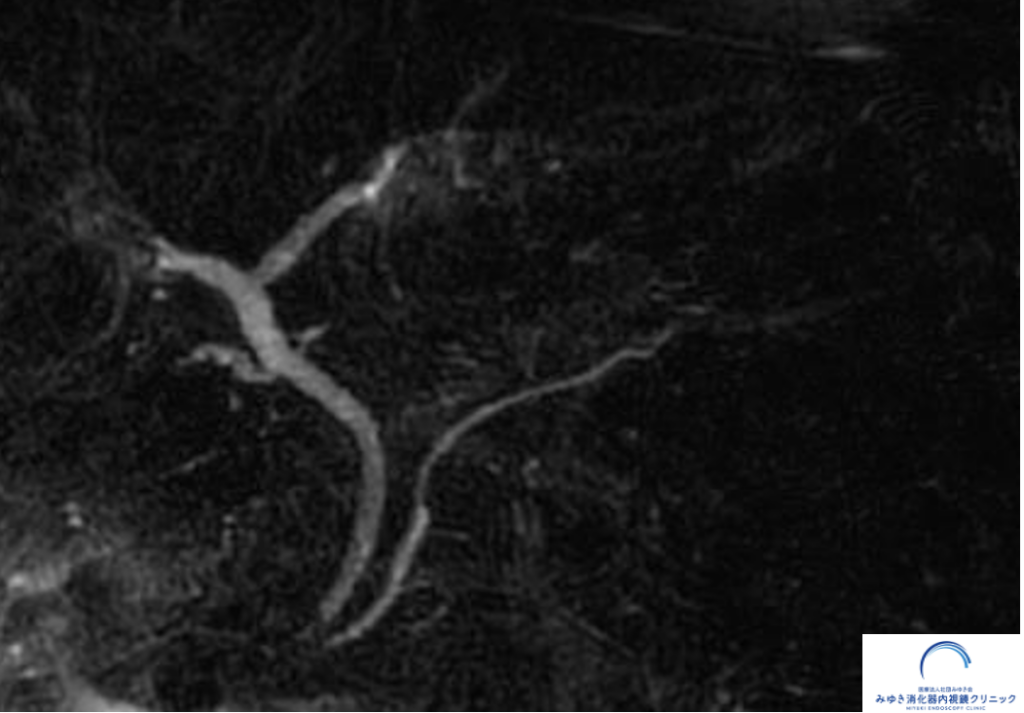

一方、超音波内視鏡検査(EUS)では

膵尾部に約10mmの小さな腫瘤

を認めました。

超音波内視鏡(EUS)で観察された膵尾部の膵神経内分泌腫瘍(膵NET)10mm

画像所見から

膵神経内分泌腫瘍(膵NET)を第一に考えました。